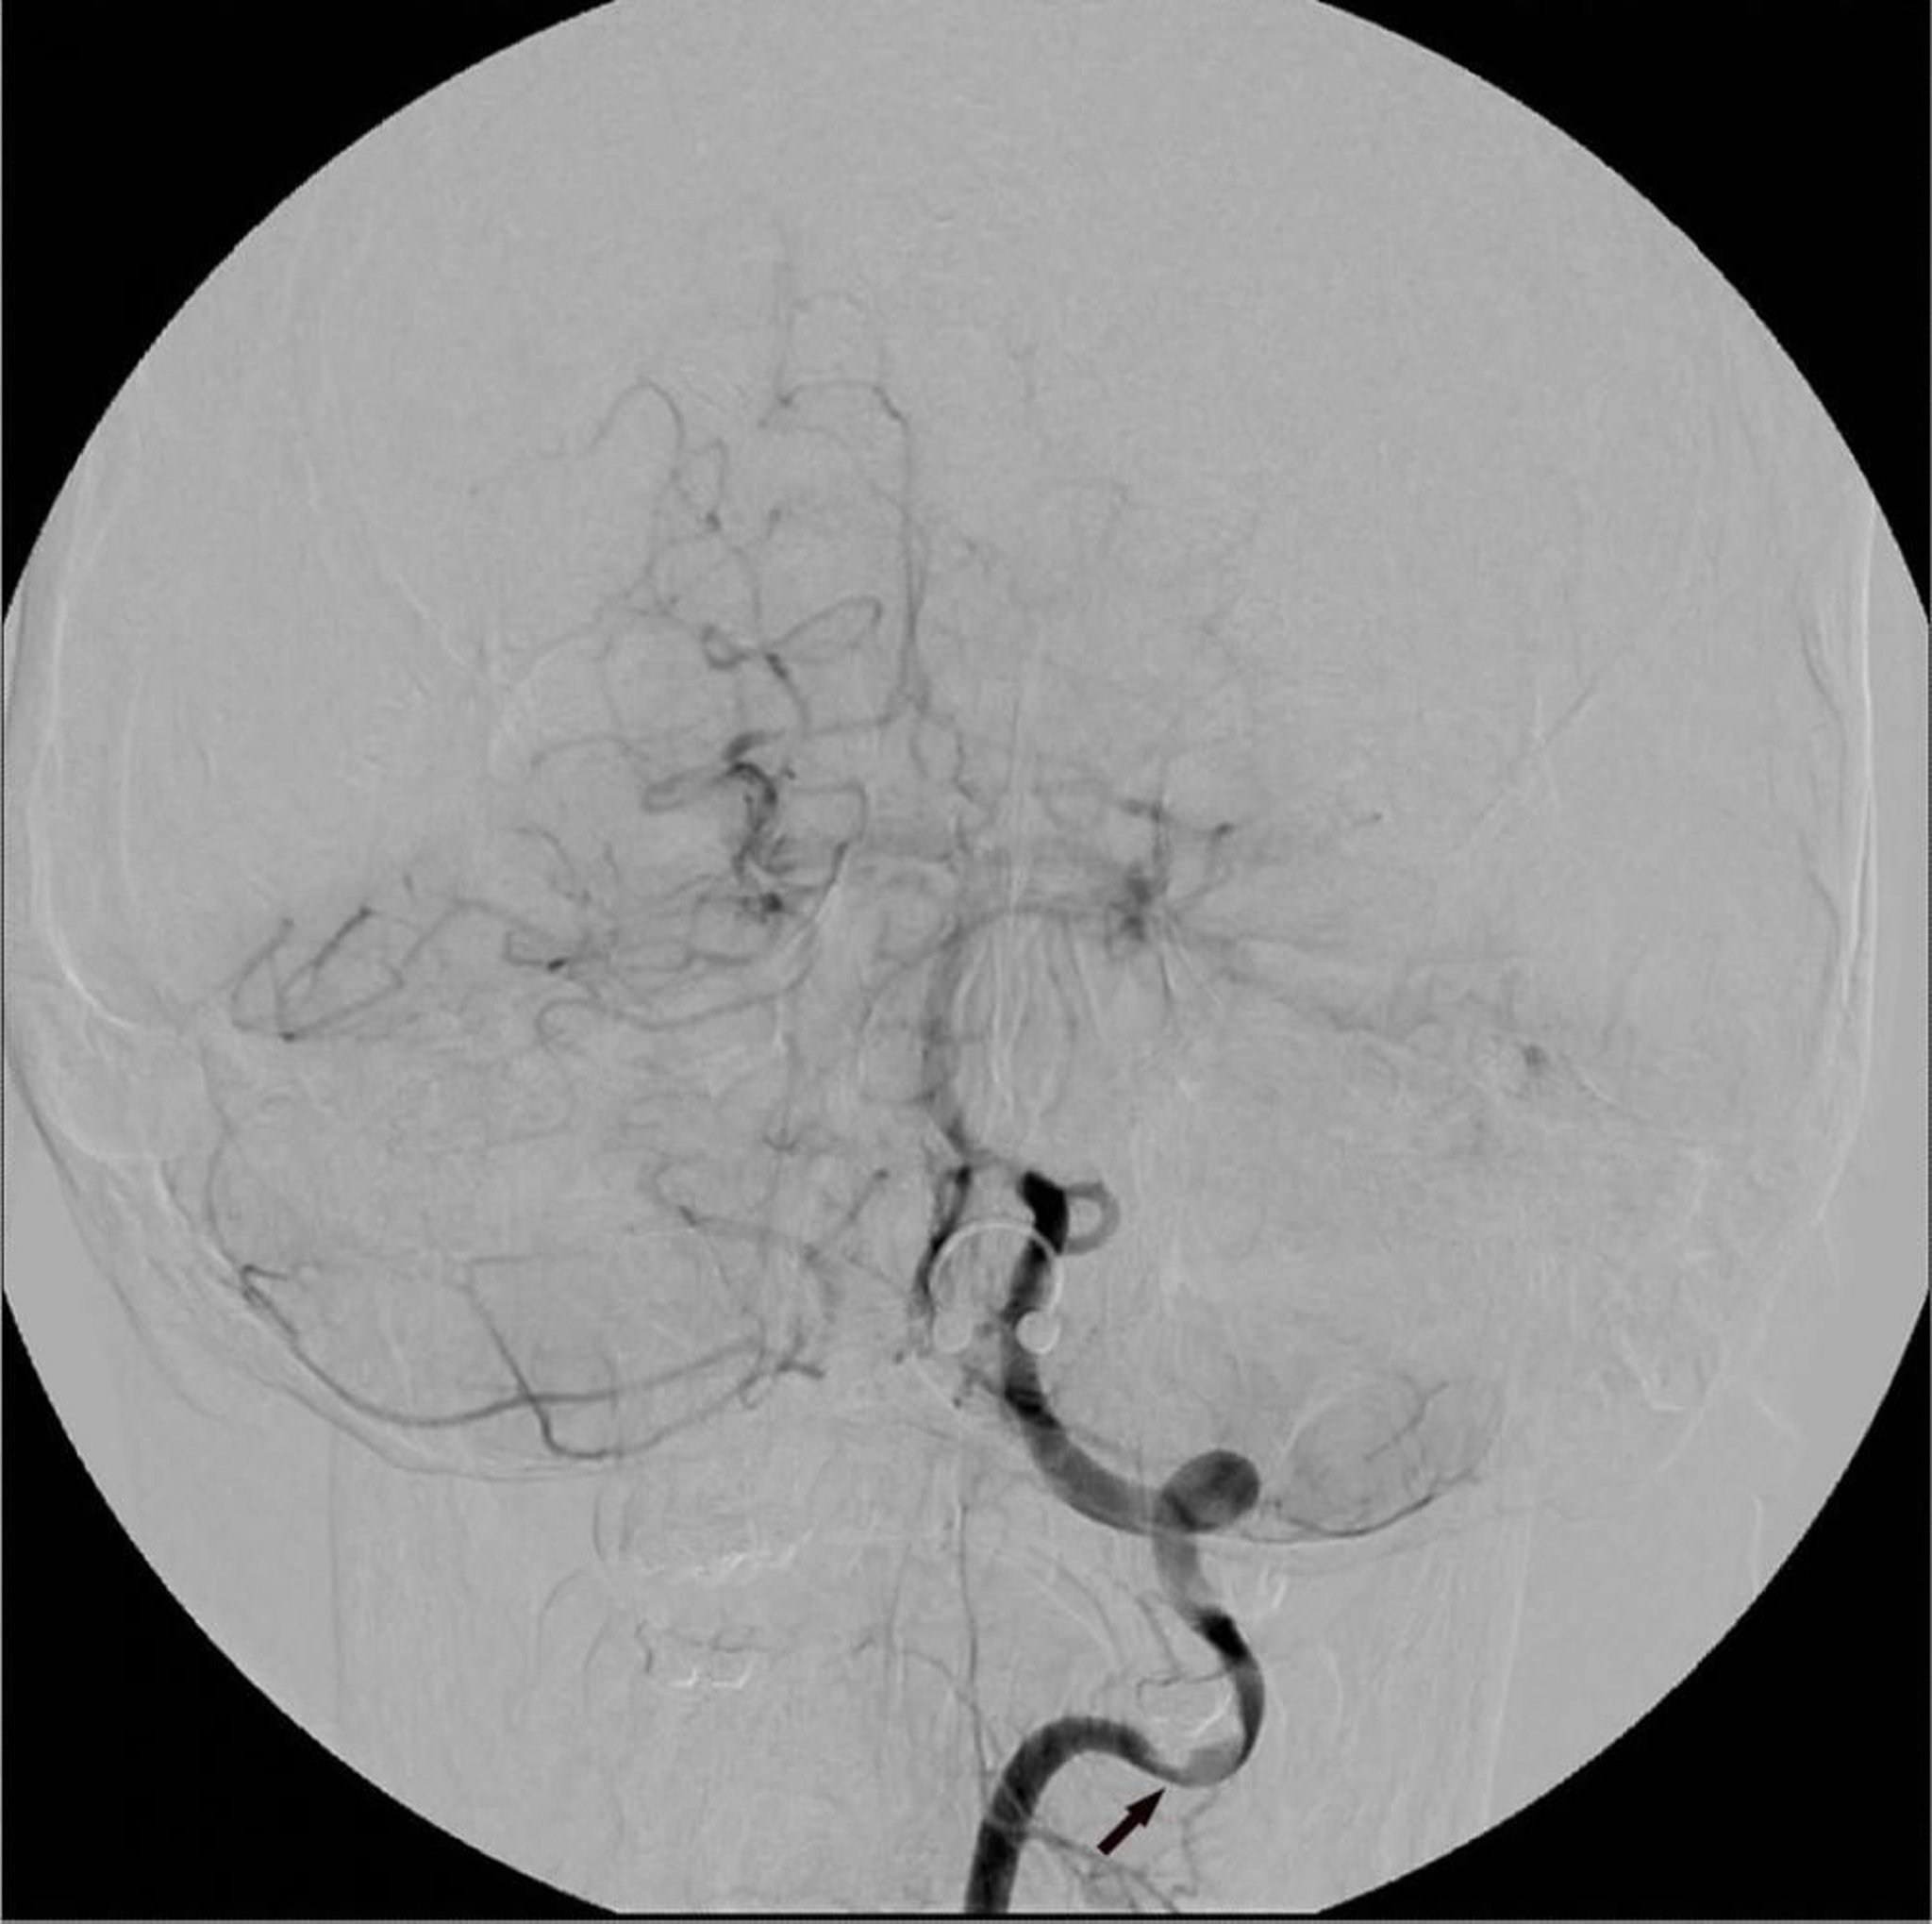

Le immagini dei vasi sanguigni vengono acquisite prima e dopo l'iniezione di contrasto; poi un computer sottrae l'immagine precontrastografica da quella postcontrastrografica. Immagini delle strutture estranee vengono così eliminate, isolando le immagini dei vasi sanguigni opacizzati dal contrasto.

L'angiografia con sottrazione digitale dell'arteria vertebrale sinistra mostra un'area focale di stenosi (freccia).

Image courtesy of Hakan Ilaslan, MD.